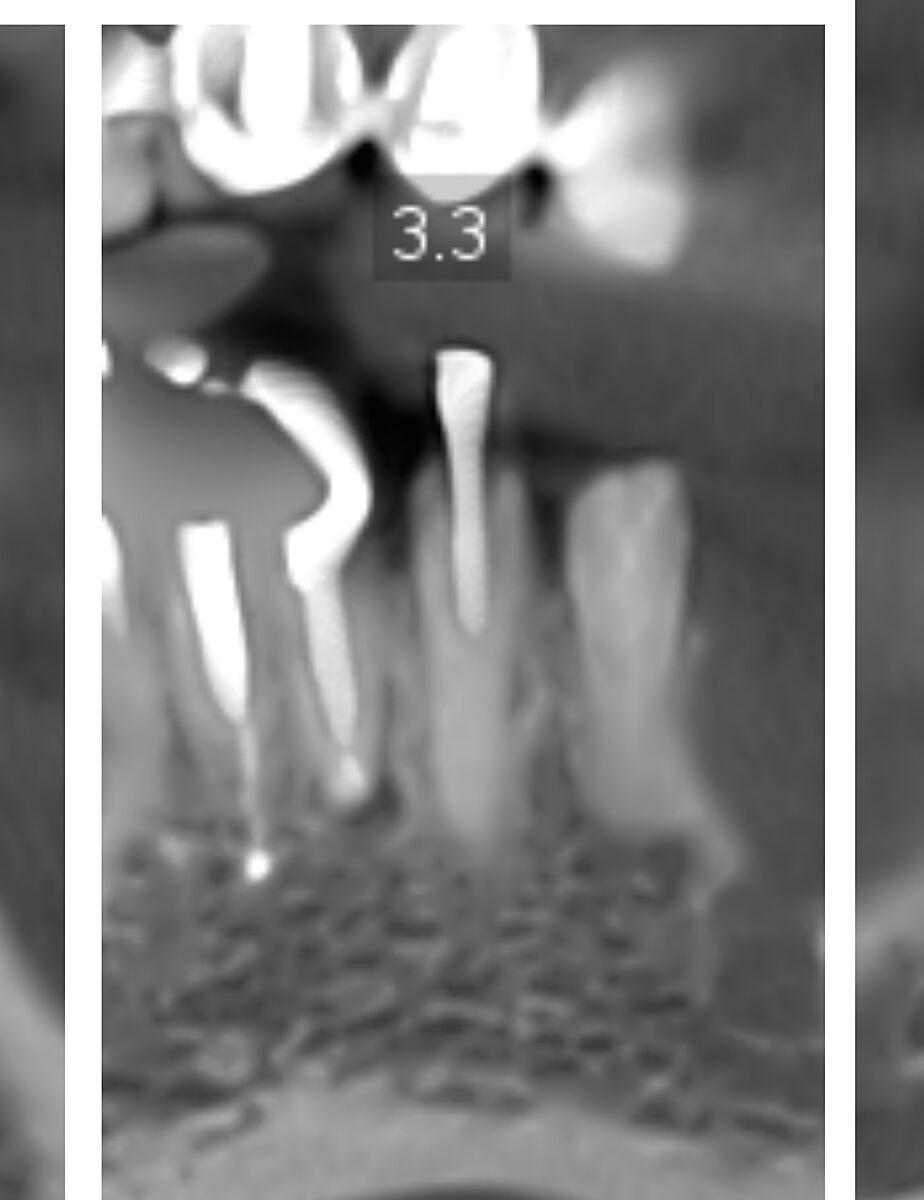

В 70 років приживуться імпланти? Ви суму можете уявити. На знімках канали і корені зубів нормальні, проліковані. Запалень нема. Простіше поміняти старі коронки і поставити незйомні мости на імпланти. По два на одну сторону. Або в такому віці можна дешевий протез, що до ясен прилипає, типу резиновий. Кожні два роки міняти.

Хоч і на штифтах, але корені нормальні, коронка зуба проглядується. У вас навіть прикус правильний при відсутності бокових зубів зверху і знизу. Відстань між щелепами де пусті місця по боках прям ідеально симетричні і не сильно просіли.

Есть здесь зубы нормальные. Есть под вопросом. Т.к. этот снимок надо смотреть полноценно , а не скрины с него. Здесь могут быть и срезы неудачные, и не всегда понятно - артефакты это или на самом деле это есть. + замеры делать надо. И это только рентгенологически... Иногда составляются планы с удалением относительно нормальных зубов для экономии средств и снижения травматичности операции...